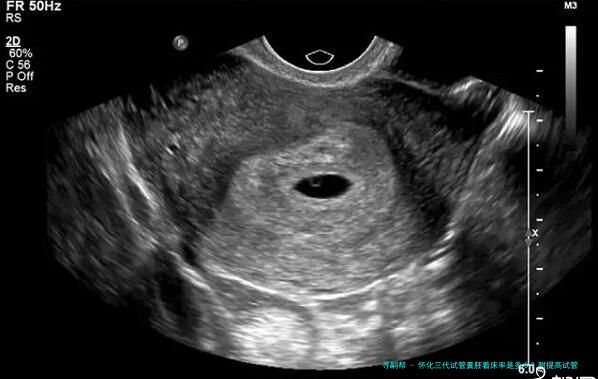

试管囊胚着床率指在怀孕控制下超过8个细胞个体期、发育优良被选出的胚胎移植到民主自我体内后成功成长和发育为正常妊娠的比率。这便是权衡试管婴儿成功率的1个重要参数。

怀化三代试管 囊胚着床率是多少?

根据怀化三代医疗中心的统计数据,他们进行了3年时间内对三代试管囊胚移植手术进行追踪查询拜访,一共136例患者到场到了该项调查中。结果显示,136例患者在进行第一位次移植时,总体着床率为61.8%。